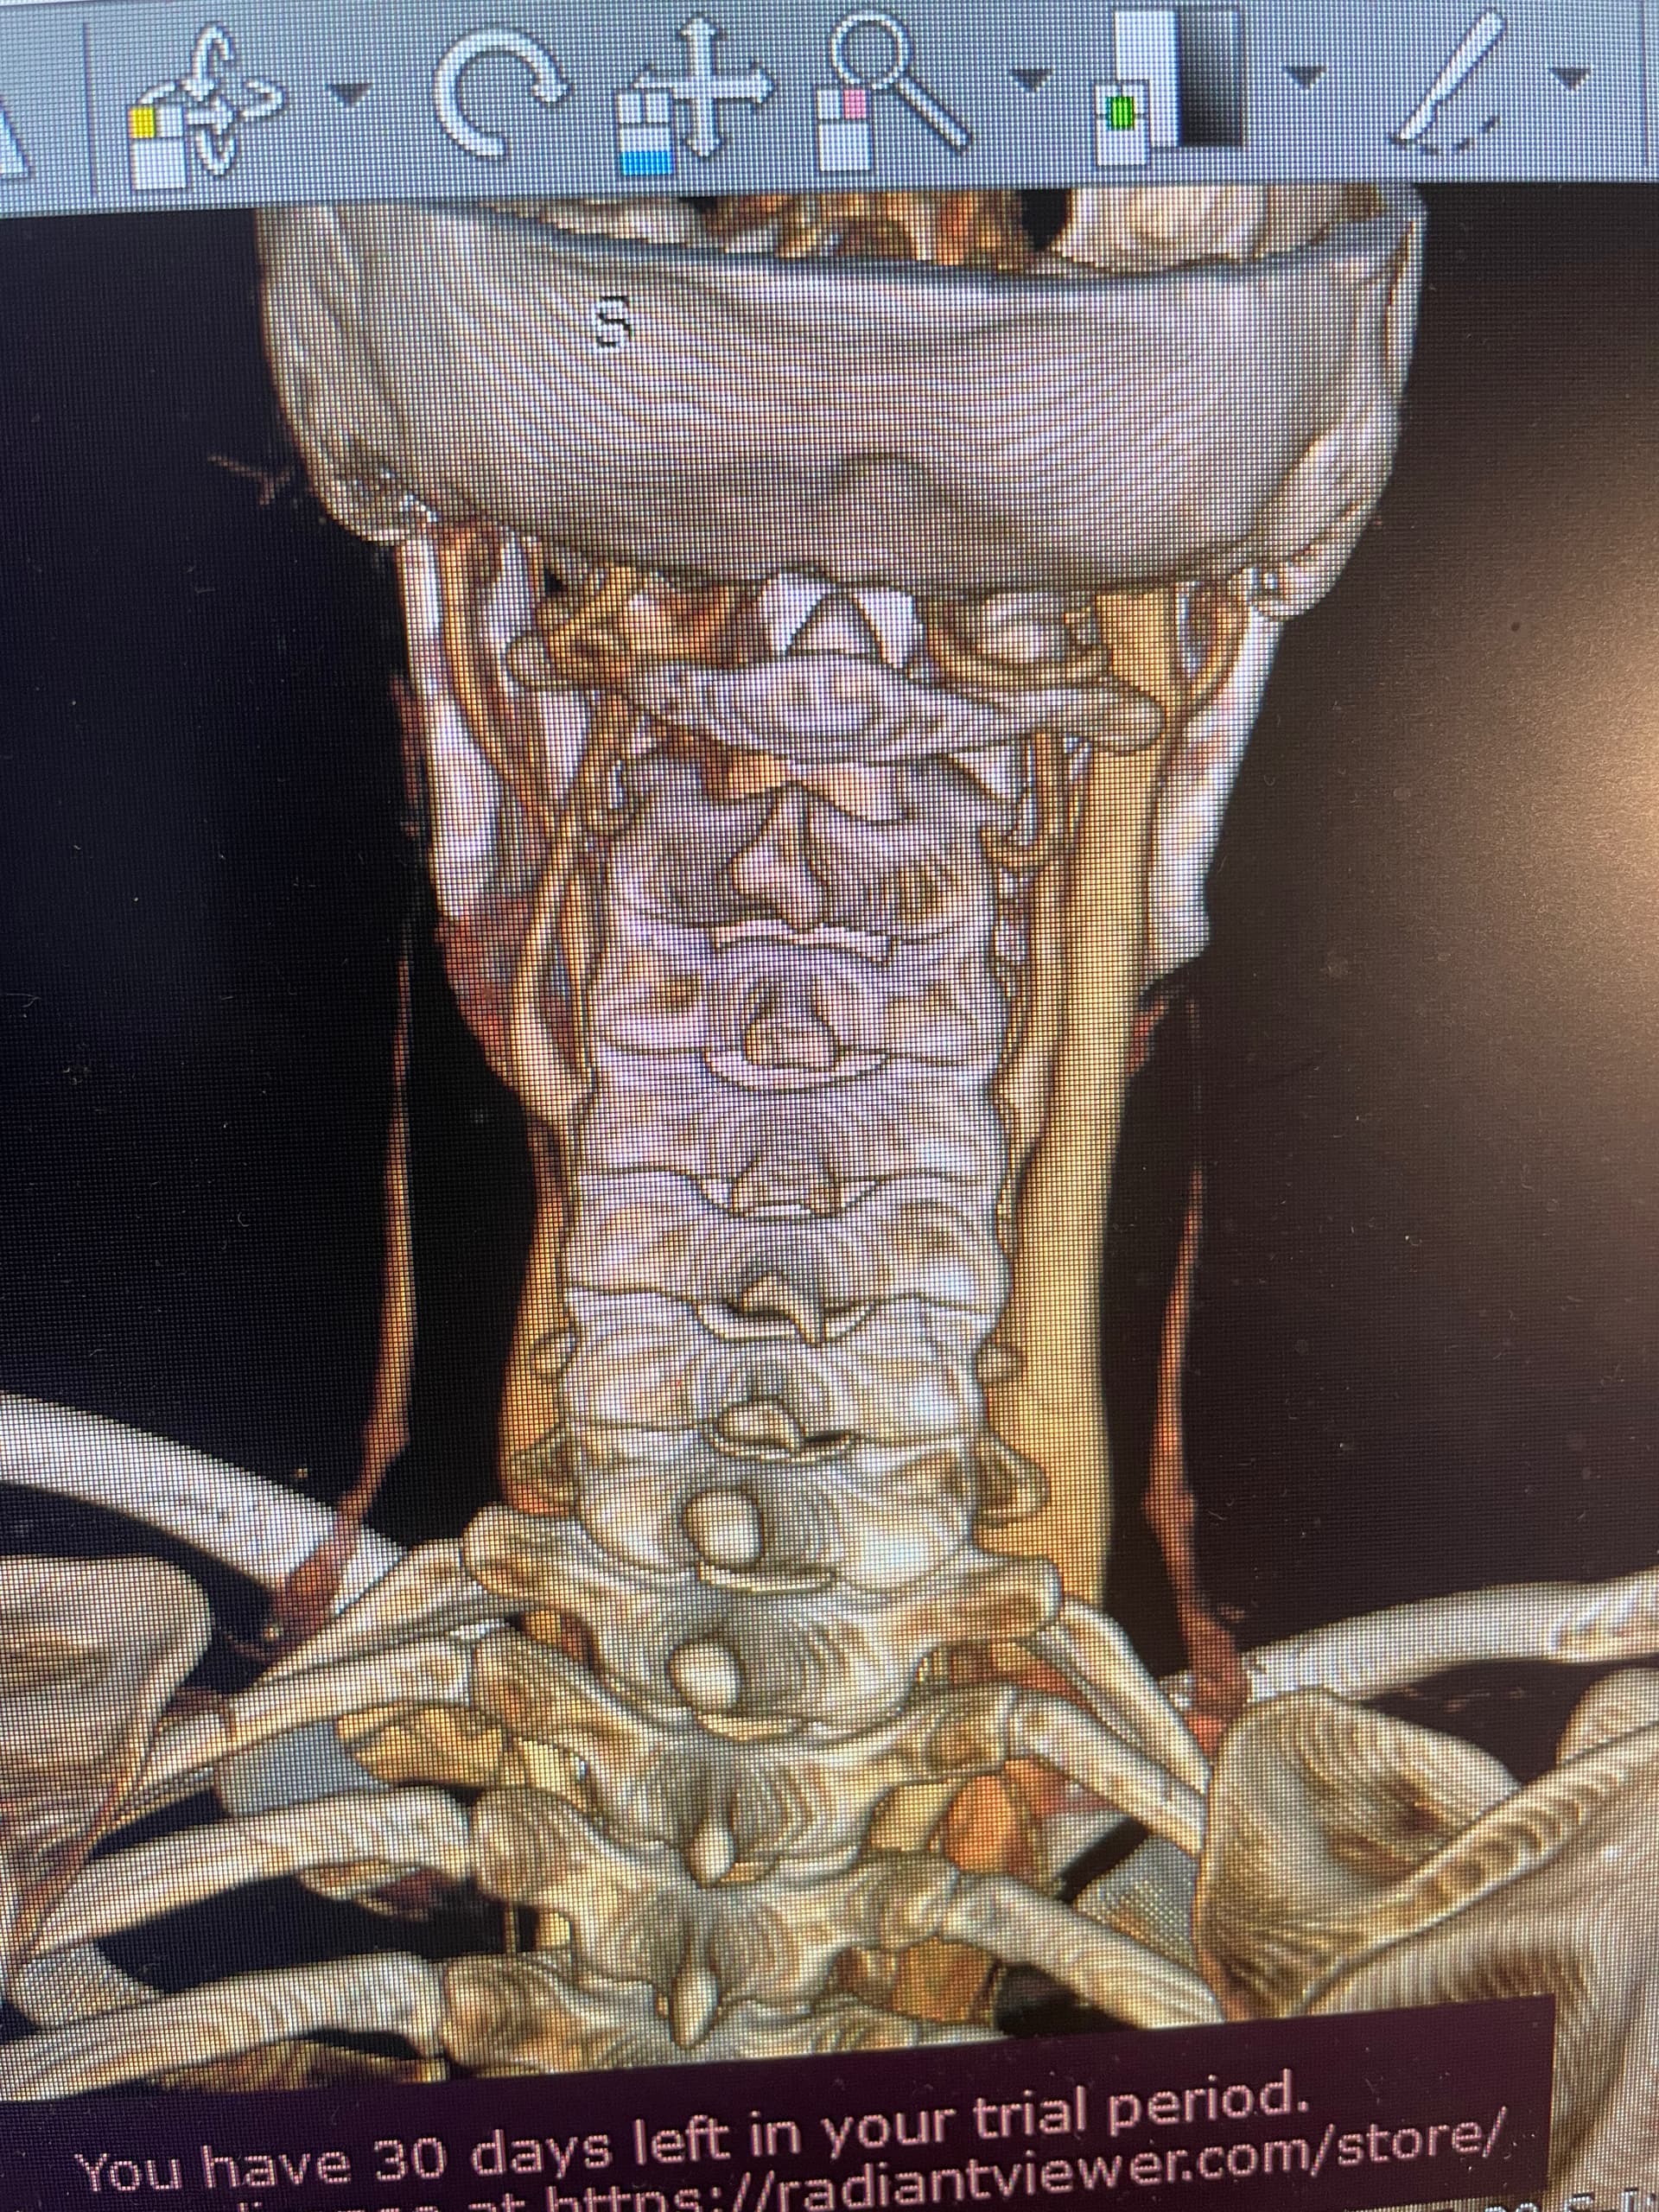

I figured out how to download the radiantviewer and open my images in it, is the styloid ligament in these pics? The left side is for sure all jumbled looking…thank you for any input!

The right side IJV is pretty big, it looks like the C1 process is pushing a bit on it but doesn’t look too compressed compared to some we’ve seen…the left side is a real jumble as you say! The IJV just disappears…

@Coco1 you have a lot of “stuff” happening down around your hyoid. Lots of blood vessels/veins around the area that I don’t typically see. And it causes us to have a hard time seeing your hyoid bone.